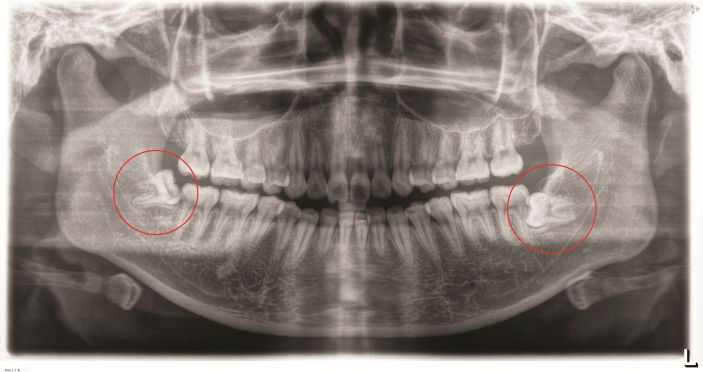

△阻生智牙。

低位埋伏阻生智齒是臨床上常見的口腔疾病,易導緻颌骨囊腫、骨髓炎和冠周炎等,影響患者的正常生活。對這種沒有咀嚼功能,且反複引發口腔問題的智牙是需要拔除的。但此類智牙的位置較深,骨阻力較大,周圍結構複雜,操作空間有限,要拔除是非常有挑戰性的。

△智牙拔除前。